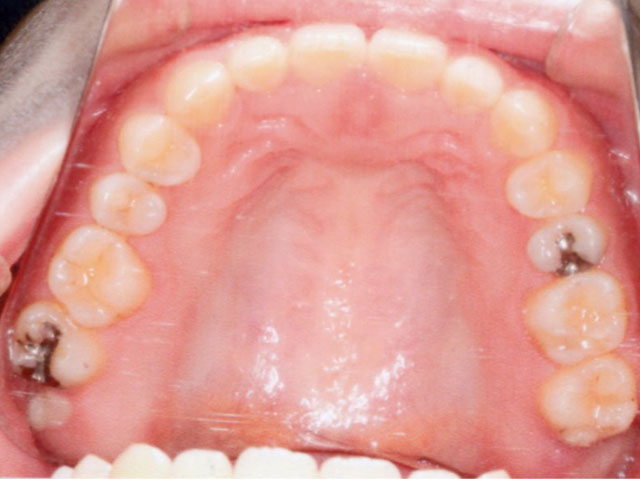

症例02【空隙歯列】

治療期間は1年11か月で、その後は保定へ移行。

舌のトレーニングについては、治療後も継続して実施しています。